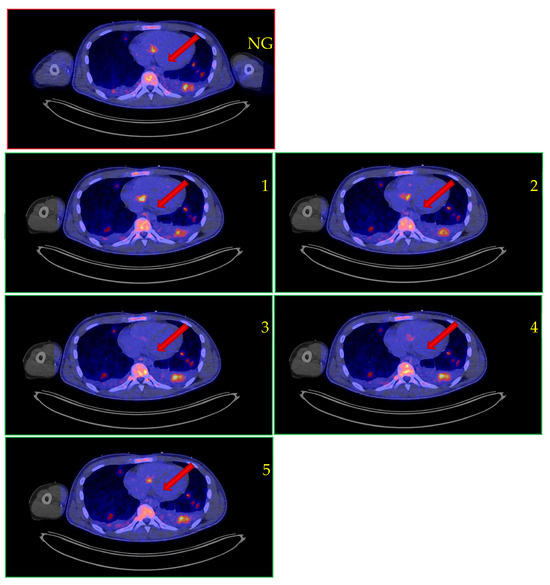

| Final Dx IE | Yes | No | Yes | Yes | Yes | No | Yes |

| Image quality | Non-gated: 3 Gated: n.a. CardioFr: 4 | Non-gated: 4 Gated: 4 CardioFr: 4 | Non-gated: 3 Gated: 4 CardioFr: n.a. | Non-gated: 2 Gated: 2 CardioFr: n.a. | Non-gated: 2 Gated: n.a. CardioFr: 3 | Non-gated: 4 Gated: 4 CardioFr: 4 | Non-gated: 3 Gated: 4 CardioFr: 4 |

| PET results | Non-gated: IE confirmed Gated: Not available CardioFreezeTM: IE confirmed (fl+) | Non-gated: No IE Gated: No IE CardioFreezeTM: No IE | Non-gated: IE confirmed Gated: IE confirmed (fl+) CardioFreezeTM: Not available | Non-gated: Equivocal Gated: Equivocal CardioFreezeTM: Not available | Non-gated: No IE Gated: Not available CardioFreezeTM: IE confirmed | Non-gated: No IE Gated: Not available CardioFreezeTM: No IE | Non-gated: IE confirmed Gated: IE confirmed (fl+) CardioFreezeTM: IE confirmed (fl+) |

| TTE, TEE, CTA | TTE: IE confirmed TEE: IE confirmed CTA: IE confirmed | TTE: No IE 1 TEE: Not performed 2 CTA: No IE | TTE: IE confirmed TEE: IE confirmed CTA: Not performed | TTE: No IE TEE: Not performed CTA: No IE | TTE: No IE TEE: IE confirmed CTA: Not performed | TTE: No IE TEE: Not performed CTA: No IE | TTE: No IE TEE: Not performed 4 CTA: Not performed |